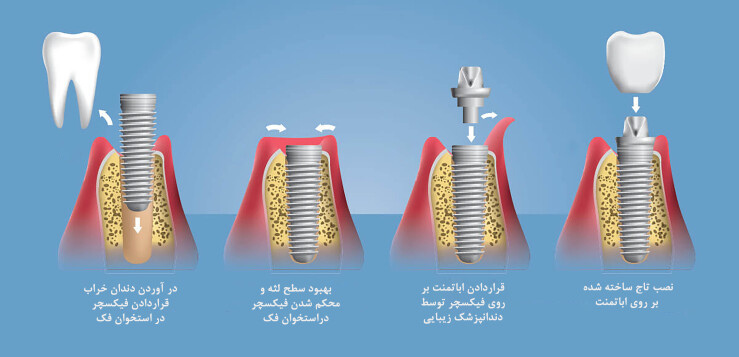

قبل از هرچیز بهتر است به طور مختصر به تعریف خود ایمپلنت بپردازیم. ایمپلنت در لغت به معنی کاشت است. در دندان پزشکی از روش ایمپلنت یا کاشت دندان برای پر کردن جای خالی دندانهای از دست رفته استفاده میشود. گاهی اوقات ممکن است دندانها بر اثر ضربه شدید، پوسیدگیهای عمیق، بیماریهای لثهای، عفونت و... از بین بروند. در چنین مواردی کاشت دندان یا ایمپلنت بهترین روش برای جایگزین کردن این دندانهاست. زیرا پایه ایمپلنت که در استخوان و لثه قرار میگیرد از جنس تیتانیوم بوده که کاملاً با بدن سازگار است و با مقاومت بسیار بالایی که دارد میتواند وظیفه ریشه دندان را به عهده بگیرد.

کاشت ایمپلنت دندانی یکی از ظریفترین و حساسترین کارهایی است که باید حتماً توسط یک جراح دندان حرفهای وبا تجربه انجام شود. زیرا هرگونه بی دقتی در کاشت پایه ایمپلنت موجب آسیب رساندن به استخوان فک بیمار خواهد شد. زمان تکمیل درمان ایمپلنت نیز تا حد زیادی به شرایط سلامتی بیمار بستگی دارد. در حالت نرمان پایه ایمپلنت(فیکسچر) در یک جلسه انجام میشود و بیمار پس از دوماه برای روکش ایمپلنت اقدام میکند مراحل انجام ایمپلنت به شرح زیر است:

1.جلسه اول معاینه و بررسی شرایط لثه و استخوان فک در عکس رادیوگرافی

2.جلسه دوم برداشت ریشه دندان معیوب و کاشت فیکسچر (پایه ایمپلنت) نصب هیلینگ "برای هر دندان 10دقیقه زمان نیاز است"

3.جلسه سوم بررسی میزان جوش خوردگی فیکسچر با استخوان فک و ساخت پروتز موقت برای زیبائی لبخند (15روز بعد از مرحله2)

4.قالب گیری برای ساخت پروتز دندان ( 1.5 تا2 ماه بعد از مرحله2)

5.بازکردن هیلینگ(درپوش فیکسچر) نصب اباتمنت(پایه ای که روکش اصلی داخل آن میرود) روی فیکسچر، امتحان کردن تاج دندان روی ایمپلنت و نهایی کردن نصب تاج دندان.(15روز بعد از مرحله4)